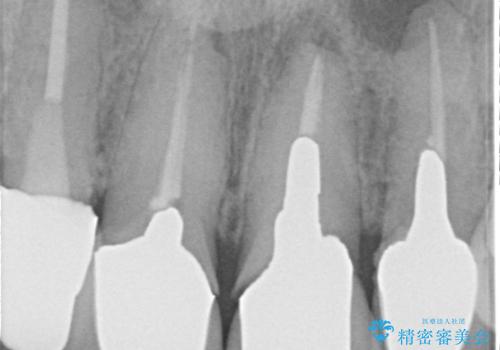

- 治療計画

- 患者様は前歯の審美的な改善を希望されて来院されました。診査の結果、左上1の歯は過去の根管治療により歯根が破折していることが判明し、保存が難しい状態でした。そのため、**長期的な予後を考慮し、抜歯と同時にインプラントを埋入する「抜歯即時インプラント」**を計画。また、隣接する左上2の歯には感染が見られたため、歯根端切除術を同時に行い、感染の除去と治癒を促しました。右上1・2については、セラミッククラウンによる審美修復を行う方針としました。

左上1は抜歯と同時にインプラントを埋入し、骨や歯ぐきの形態を維持しながら治療を進めました。左上2は歯根端切除術により感染部位を除去し、保存治療を実施。右上1・2も含めた前歯4本をセラミッククラウンで修復し、自然な色調と形態を再現しました。治療後は、噛み合わせの安定とともに、美しく自然な前歯を回復することができました。患者様からも「見た目がとても自然で、自信を持って笑えるようになった」と喜びの声をいただきました。